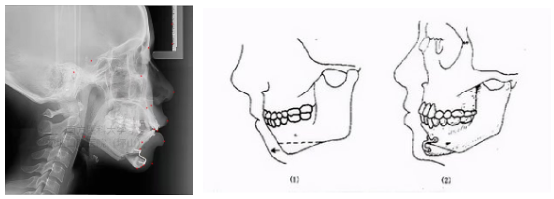

▲根尖下截骨术数字化设计

(粉色半透明为术前模型)

▲颏成形术示意图

原本短了的往外拉

原本长了就往里推